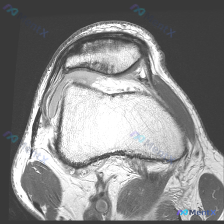

刚拿到一份膝关节冠状位T1加权MRI,问题一开始问的是「是否存在半月板异常」,整理了完整的读片和分析思路分享给大家: 一、影像基本信息 本次提供的是膝关节MRI冠状位T1加权影像,按照结构顺序逐一读片: 1. 骨与软骨:股骨远端、胫骨近端骨皮质完整,黄骨髓信号正常,未见明确骨折、骨挫伤或骨质破坏,关...